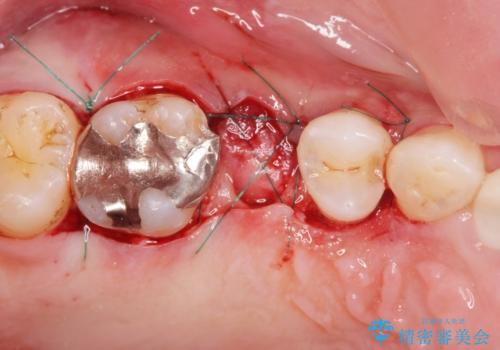

抜歯を行い、咬合機能の回復を行いますが、咬合関係や非常に強い噛み合わせの問題をふまえ、咬合面をメタルにしたメタルボンドブリッジで治療を行うこととしました。

また噛み合わせが深くブリッジの強度が十分に確保できないことから、抜歯時に歯周外科を行うことで十分に安定したクラウン装着をできるような処置を行っています。

術前・術後でブリッジ治療をした部分の歯肉ラインを整えたことで安定したブリッジを製作することができました。